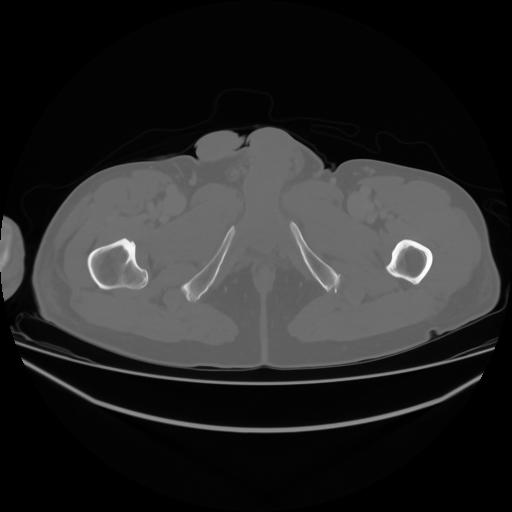

4 CUERPO,CE,Axial,3.0,CUERPO,,